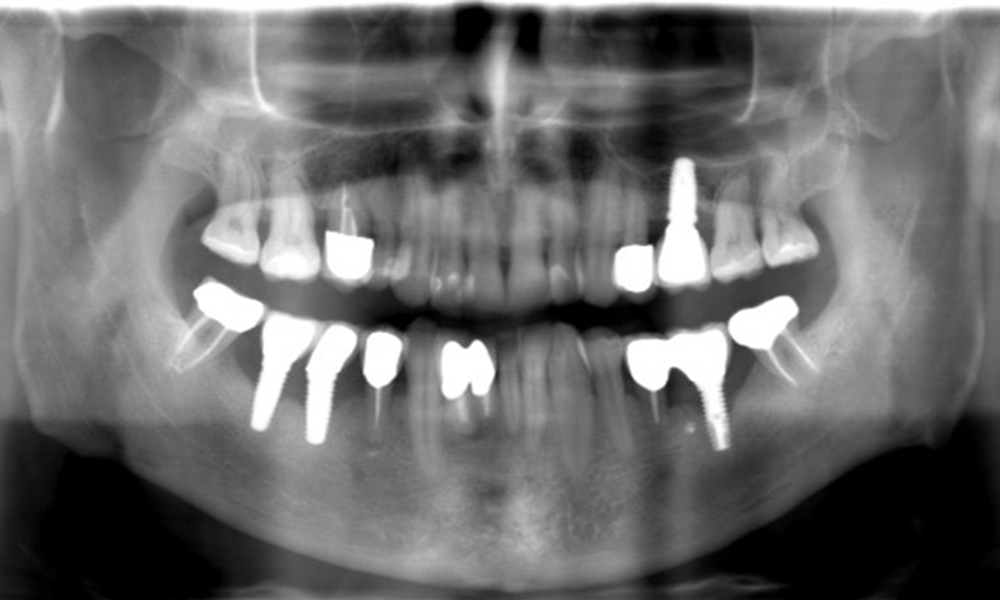

Ein 52-jähriger Patient stellt sich zur Präventionssitzung vor. Der Patient hat keine Allgemeinerkrankungen und nimmt keine Medikamente ein. Er hat verschiedene zahnärztliche Versorgungen und zudem zwei aktive kariöse Läsionen. Außerdem verfügt der Patient über vier Implantate (2., 3. und 4. Quadrant). Es zeigt sich eine parodontale Vorerkrankung (Stadium IV, Grad B). Derzeit herrschen stabile parodontale Verhältnisse, lediglich am Implantat regio 36 zeigen sich Sondierungstiefen (ST) von 5 mm. Zudem lässt sich eine Gingivitis feststellen.

Der Patient zeigt keine besonderen anamnestischen Risikofaktoren mit spezifischen zahnmedizinischen Auswirkungen. Daher ist der aus der Mundgesundheit ermittelte Bedarf maßgebend. Hierbei zeigt sich am Implantat im 3. Quadranten ST von 5 mm und im Röntgenbild eine Zunahme des Knochenverlustes. Der Patient hat zudem eine aktuell stabile parodontale Vorerkrankung und zwei aktive initialkariöse Läsionen.

Röntgenaufnahme zeigt Verlauf des Knochenabbaus

"Die Röntgenaufnahmen zeigen den Verlauf des Knochenabbaus. OPG vom 29.06.2020 (links) und OPG vom 26.02.2024 (rechts)

OPG: 26.02.2024 ZF: 18.01.2024